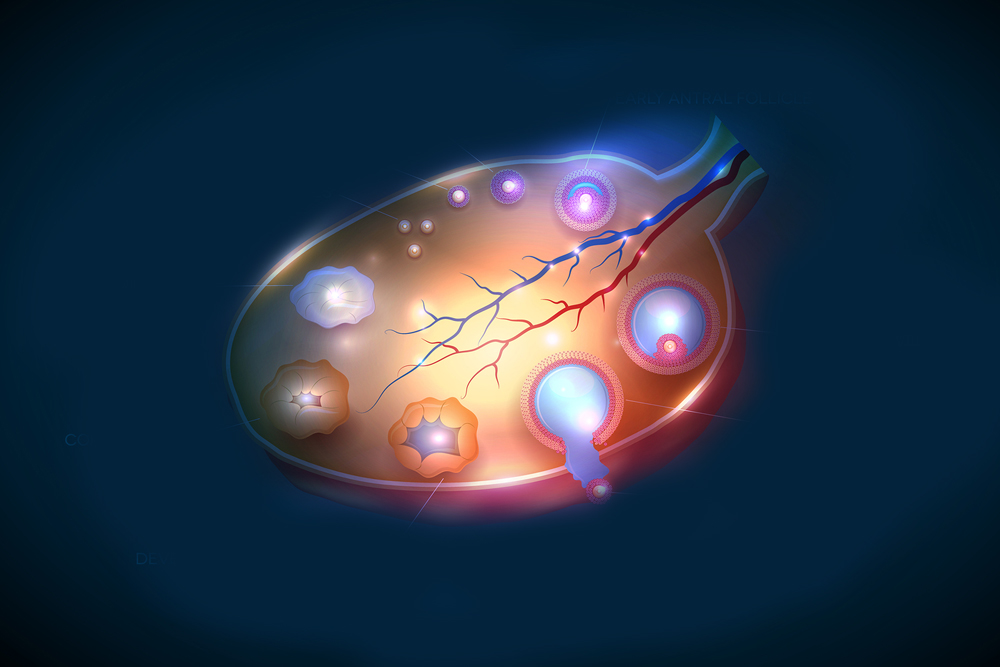

Созревание фолликула в яичнике: этапы и процессы